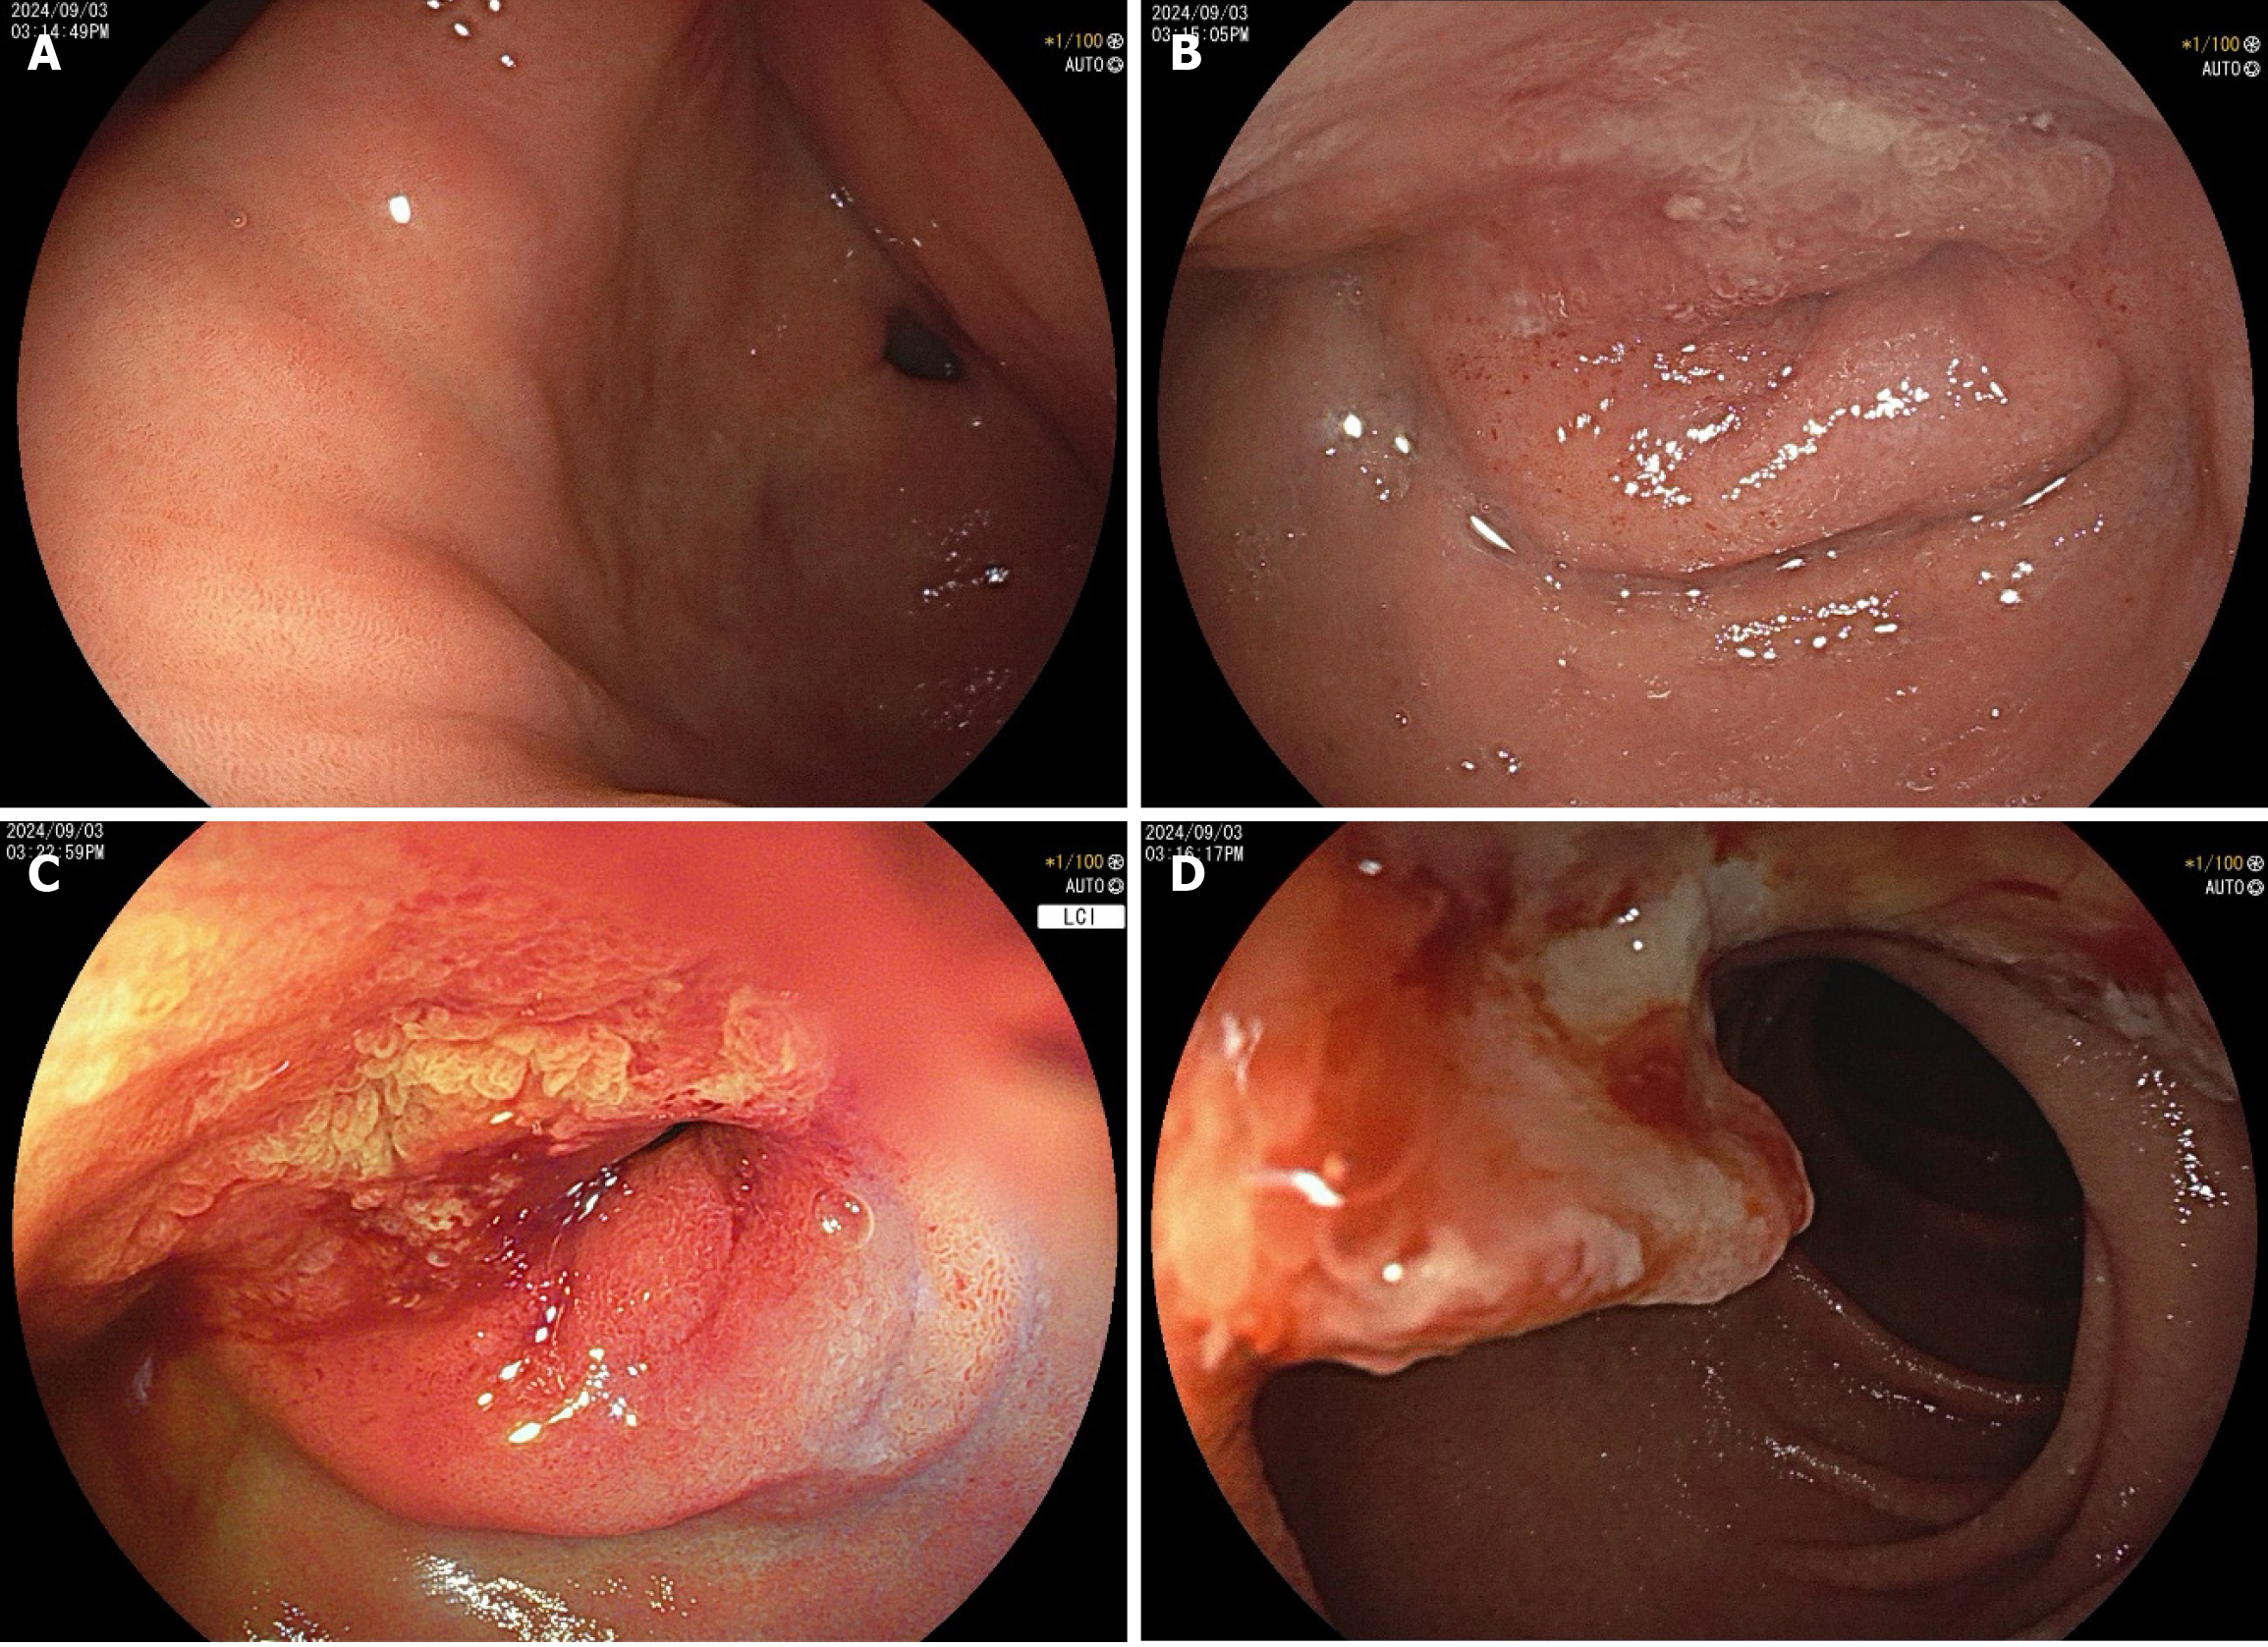

An upper endoscopy revealed the following: (1) A large, soft submucosal lesion involving the pylorus and greater curvature of the gastric antrum, with preserved luminal patency; (2) An ulcerated lesion at the duodenal bulb-descending junction, with luminal narrowing and raised margins (Figure 3); and (3) Endoscopic ultrasonography (EUS) identified a 7 cm × 4.8 cm mixed cystic-solid mass with clear demarcation from the adjacent organs but a loss of interface with the fourth layer of the gastric wall (Figure 4).

Biopsy of the ulcer confirmed moderately differentiated adenocarcinoma, obviating the need for the planned endoscopic ultrasound-guided fine needle aspiration (EUS-FNA). Notably, the patient’s CA19-9 level decreased to 43 U/mL pre

Among the reviewed cases, we found that the morphology of adenocarcinomas arising from HP varies considerably. Preoperative diagnosis of a malignant ectopic pancreas with stenotic or submucosal tumor (SMT) morphology and no ulceration can be difficult using imaging studies such as CT and radiography. This is because imaging can only indicate the presence of a mass; it cannot determine its nature. For this reason, most of the reviewed cases of adenocarcinomas arising from an ectopic pancreas were resected as SMTs with tentative diagnoses of gastrointestinal stromal tumor, lymphoma, or other[4]. The mass in our patient had a predominantly SMT-like appearance, with focal ulceration in the duodenum. Malignant transformation of an HP usually occurs intramurally, and involvement of the overlying mucosa occurs late in the course of the disease. While upper endoscopy with conventional biopsy at the location of the tumor rupture can obtain pathological findings, it often fails in SMT-like lesions. The utility of EUS-FNA and endoscopic mucosal resection with cap for histological diagnosis has been demonstrated for many gastrointestinal and pancreatic malignancies. EUS is especially helpful in the diagnosis of SMTs. EUS-FNA combined with immunohistochemistry can achieve a higher histological diagnostic rate. An endoscopic mucosal resection with cap is an endoscopic mucosal resection performed using a panendoscope with a fitted transparent plastic cap. This, followed by a biopsy[4], should be considered before selecting a treatment approach. Matsuki et al[5] have reported a case with no distinct cystic lesion on EUS due to its obscuration by severe stenosis. Therefore, although EUS is generally helpful for the diagnosis of SMTs, the location of the tumor may determine the clarity of the scan. The detection of cystic components inside the tumor is helpful for the diagnosis of HP[5].